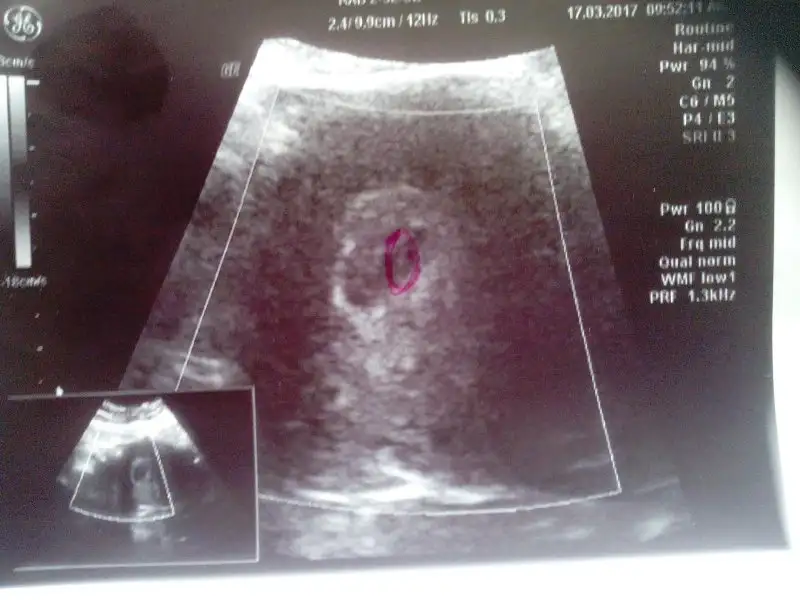

Kizlar banada yorum yapin,6+0 karindan